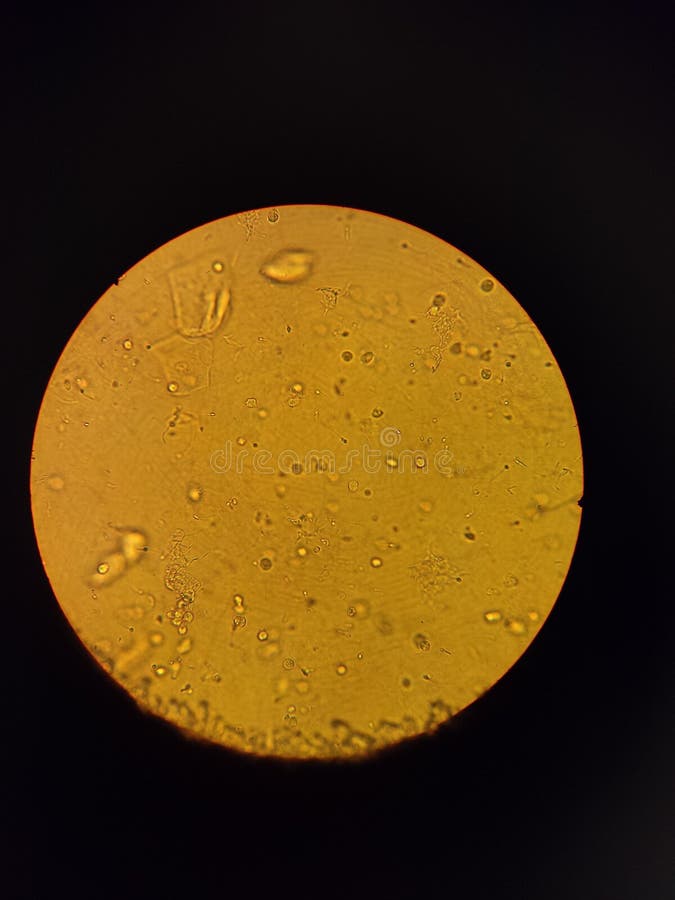

Particulas Blancas En La Orina, Que hacer ante la presencia de arenilla en orina Dra Marcela Munizaga 06-03-2021, 4.21 MB, 03:04, 30,769, parasusaludtv, 2021-03-06T14:45:02.000000Z, 3, Cristales en la orina: Tipos, Síntomas, causas, Remedios caseros | SaludAIO, saludaio.com, 1200 x 900, jpeg, WebLas posibles causas de partículas blancas o sedimentos en la orina incluyen: 1. Embarazo. Durante el embarazo, hay una variedad de cambios hormonales que. WebLos cálculos renales son una concreción sólida que se forma en el riñón a partir de partículas que se encuentran en la orina. Se trata de fragmentos que pueden ser tan., 20, particulas-blancas-en-la-orina, Novedades y Muebles WebLas posibles causas de partículas blancas o sedimentos en la orina incluyen: 1. Embarazo. Durante el embarazo, hay una variedad de cambios hormonales que. WebLos cálculos renales son una concreción sólida que se forma en el riñón a partir de partículas que se encuentran en la orina. Se trata de fragmentos que pueden ser tan.

WebSi presentas partículas blancas en la orina puede deberse a la presencia de cristales, esto se produce cuando la orina se concentra por falta de una buena hidratación. Se deben. WebParticulas blancas en la orina: Mamis a alguna le paso. Me parece super raro , cuando orino veo en el baño particulas blancas como si fuera pedasos de piel no se.. WebVer partículas blancas en la orina puede ser una experiencia alarmante. Después de todo, no es algo que ves todos los días. Este síntoma puede ser causado por muchas cosas.. WebLas partículas blancas que flotan en la orina son absolutamente "una condición común". Dicho esto, no se preocupe. Por el. Las posibles causas de partículas blancas "flotante". WebPorque yo me coloco óvulos de progesterona a la noche y al otro día en la orina se ven gotitas blancas, que si bien son de la vagina, al estar cerca el duct urinario.

WebLas partículas blancas que flotan en la orina son absolutamente "una condición común". Dicho esto, no se preocupe. Por el. Las posibles causas de partículas blancas "flotante". WebPorque yo me coloco óvulos de progesterona a la noche y al otro día en la orina se ven gotitas blancas, que si bien son de la vagina, al estar cerca el duct urinario. WebSi nota partículas blancas en la orina, es probable que sea por secreción genital o un problema en su tracto urinario, como cálculos renales o posible.